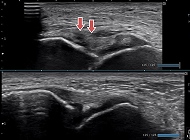

当院でのエコー画像

活用例・適応症状